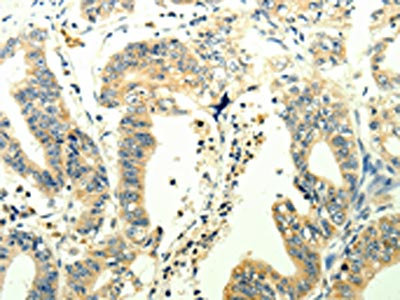

• The image on the left is immunohistochemistry of paraffin-embedded Human gastic cancer tissue using CSB-PA939437(TRPM7 Antibody) at dilution 1/25, on the right is treated with synthetic peptide. (Original magnification: ×200)

• The image on the left is immunohistochemistry of paraffin-embedded Human liver cancer tissue using CSB-PA939437(TRPM7 Antibody) at dilution 1/25, on the right is treated with synthetic peptide. (Original magnification: ×200)